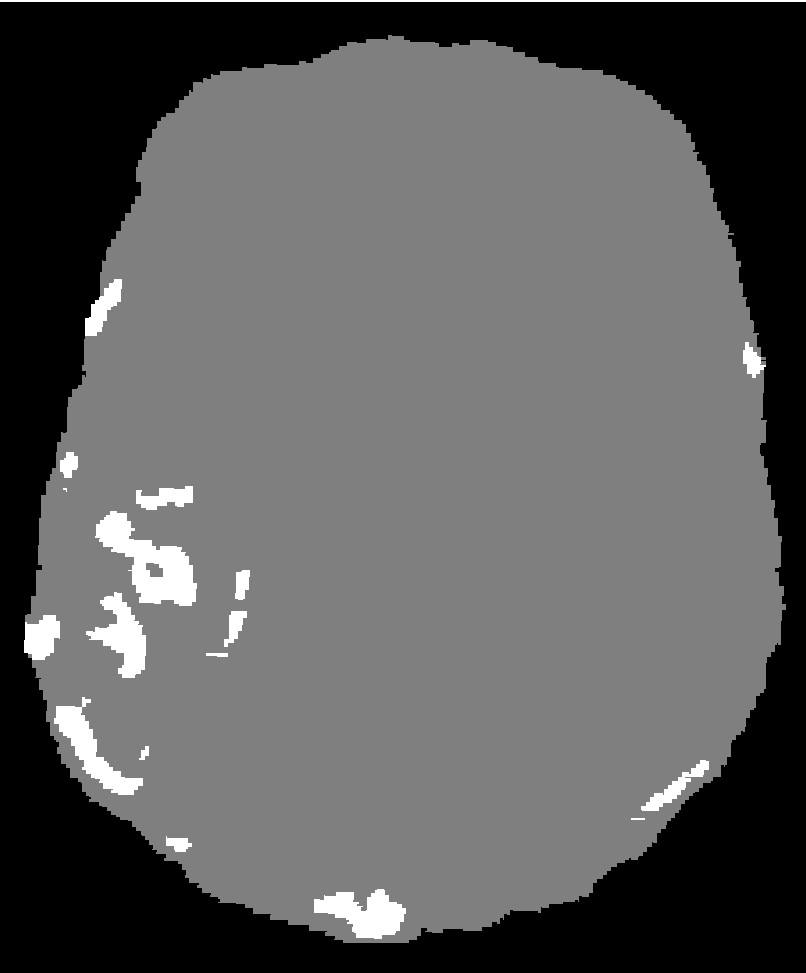

The mesh fidelity is qualitatively evaluated on AVM data (case 3). For this purpose, the AVM mesh is first extracted from the multi-material mesh and then superimposed on the AVM segmentation (Figure 22). The closer the mesh surface is to the boundary of the segmented AVM image, the higher the fidelity. The LD method achieves high fidelity because it completely resolves the vessels (it creates a voxelized mesh surface). Nevertheless, Figure 22e indicates a small shift in the output mesh in relation to the input image, most likely due to image resampling. CLEAVER resolves most of the vessel structures, but the generated mesh is noticeably shifted (Figure 22d). CBC3D achieves satisfactory fidelity. CBC3D’s mesh topological checks are turned off to avoid further red-green subdivisions, keeping the element count low.

Refer to caption

(a) AVM image

(b) CBC3D

(c) CGAL

(d) CLEAVER

(e) LD

(f) PODM

Figure 22: Qualitative evaluation on the fidelity of AVM mesh. Figures LABEL:sub@AVMFidelityOne- LABEL:sub@AVMFidelityFive depict the AVM mesh (red) superimposed on the AVM segmentation (blue). The closer the mesh surface is to the boundary of the segmented material, the higher the fidelity.